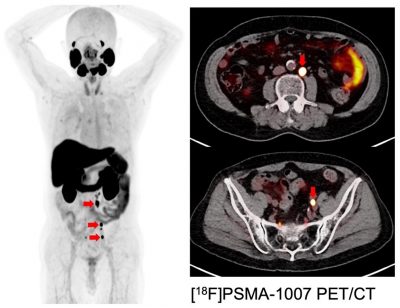

Figure 2. Companion PET images targeting PSMA:

Hormone refractory prostate cancer with multiple lymph node metastases (red arrow)